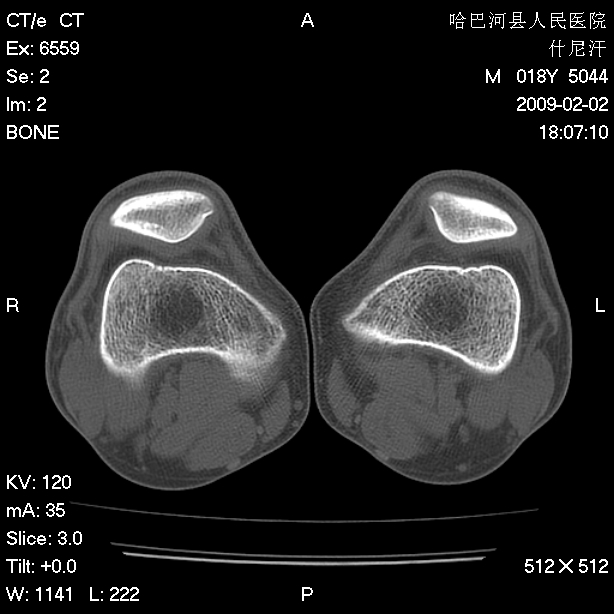

标题: CT17889:外伤后右膝关节反复疼痛3年余 [打印本页]

标题: CT17889:外伤后右膝关节反复疼痛3年余

ct未见明显异常。关节腔未见明显积液,半月板未见明显撕裂。但最好还是mri看看韧带及半月板情况。